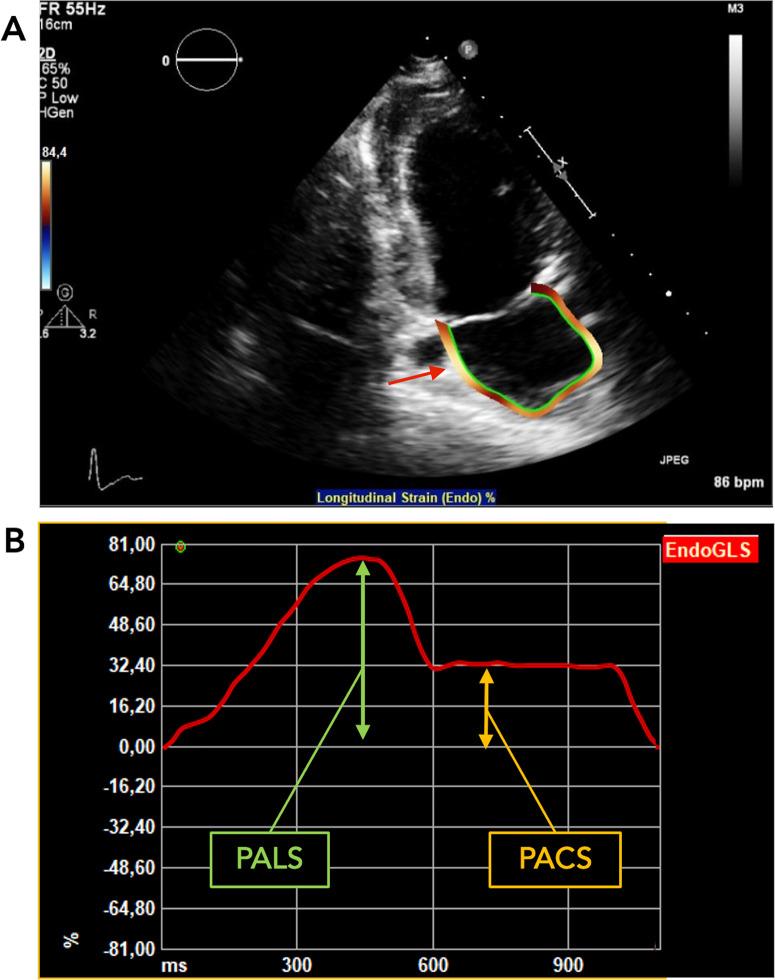

Atrial arrhythmias are an important cause of morbidity and mortality in adults with congenital heart disease (ACHD). In acquired heart disease, the left atrial (LA) strain has been shown to predict supraventricular tachyarrhythmias (SVT). This study aimed to investigate whether reduced LA strain is associated with SVT in ACHD patients. This retrospective, single-center cohort study collected baseline clinical and echocardiographic data of 206 ACHD patients (157 left heart defect, 49 right heart defect). Patients with sinus rhythm at baseline and a 5-year follow-up (median age 29, IQR 22-41 years) were included. Diagnosis of sustained SVT was determined from clinical reports during the follow-up period. New or recurrent sustained SVT occurred in 16 patients (7.8%, median follow-up of 6.2 years). Patients who developed SVT were older, more likely to have diastolic dysfunction, and had larger LA dimensions, left ventricular mass, and a lower peak LA longitudinal strain (PALS). Lower PALS was associated with higher risk of SVT in patients with left and right heart defects. Patients in the lowest quartile for PALS had a 15.9-fold higher hazard ratio of SVT (95% confidence interval, 4.5 to 56.0, p < 0.001) in comparison with the top three quartiles. PALS provides information about the occurrence of SVT in the ACHD population. Including measurement of LA strain in the follow-up of these patients may allow to better identify patients at risk of future atrial arrhythmias.

房性心律失常是成人先天性心脏病(ACHD)患者发病率和死亡率的重要原因。在获得性心脏病中,左心房(LA)应变已被证明可预测室上性心动过速(SVT)。本研究旨在探讨 LA 应变降低是否与 ACHD 患者的 SVT 相关。这项回顾性、单中心队列研究收集了 206 例 ACHD 患者(157 例左心缺陷,49 例右心缺陷)的基线临床和超声心动图数据。纳入了在基线和 5 年随访时(中位年龄 29 岁,IQR 22-41 岁)窦性心律的患者。在随访期间根据临床报告确定持续性 SVT 的诊断。16 例患者(7.8%)新发或复发性持续性 SVT。发生 SVT 的患者年龄较大,更可能存在舒张功能障碍,且 LA 尺寸、左心室质量更大,峰值 LA 纵向应变(PALS)更低。较低的 PALS 与左、右心缺陷患者发生 SVT 的风险增加相关。PALS 最低四分位数的患者发生 SVT 的危险比为 15.9 倍(95%置信区间,4.5 至 56.0,p<0.001),高于前三四分位数。PALS 提供了 ACHD 人群中 SVT 发生的信息。在这些患者的随访中包括 LA 应变的测量可能有助于更好地识别未来发生心房性心律失常的风险患者。